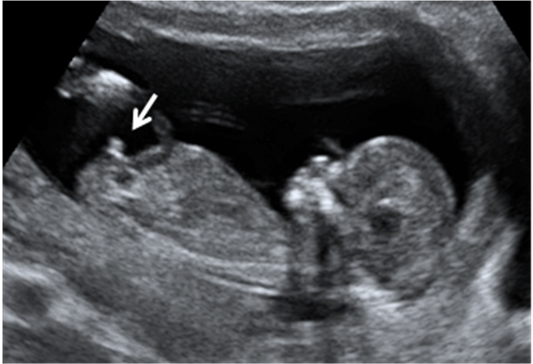

La ecografía de la semana 12 de embarazo permite diagnosticar casos de fetos siameses. Esta anomalía surge cuando un óvulo fecundado se divide en dos, como los gemelos monocigóticos, pero días más tarde, de forma que no llegan a separarse del todo. Comparten aparte de la bolsa amniótica y la placenta, algún órgano.